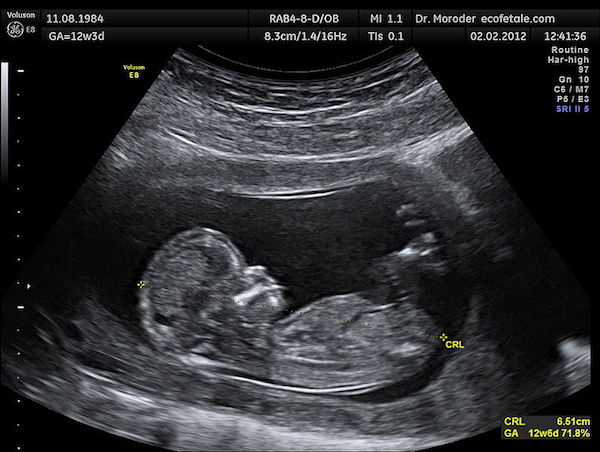

2017年12月07日墮胎一直是社會中極具爭議的話題,一位在婦科工作的護理師就發文表示,他們所看過的事經常「晚上做惡夢」,她表示自己不否定人工流產,只想提醒大家人流真的要提早,否則對孩子是莫大傷害!

▼護理師說,她看過許多心痛的案例,「16歲的女孩選擇23週再流產,只為了驗DNA來提告當天參加亂交趴的男性,因為根本不記得孩子的爸是誰,孩子流出的時候,努力的掙扎,努力的想呼吸…」

▼「看過把孩子硬留著,最後被爸媽發現,只能選擇13週引產,」她又舉例道,「已經24歲的、負不起責任的女孩,選擇不手術,結果孩子的頭被醫生夾斷了,身體卻還是動了幾下…」

▼她提到自己不反對流產,「畢竟孩子生下來如果不會養,那隻會更慘,但為什麼不早一點呢?」她指出周數大一點的嬰兒往往已經會哭、會動,但許多流掉的嬰兒只能留在盒子裡,痛苦的走…

她深深勸導道:「拜託各位,如果你還沒準備好一切,如果你沒有肩膀負起責任,請你不要懷孕,如果你懷孕了,請你在心跳開始前(6週)到診所、到醫院處理。」她也提到月經遲到的一定要驗孕,不要只是單純覺得太累月經晚來,等發現時可能已經太晚。